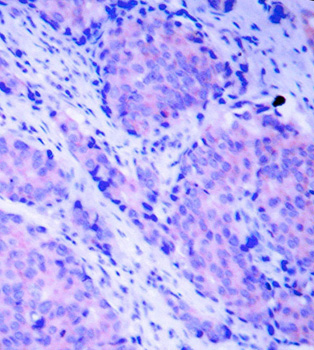

• AP0426: image 2

Immunohistochemical analysis of paraffin-embedded human breast carcinoma tissue, using Phospho-PDPK1-S241 antibody.